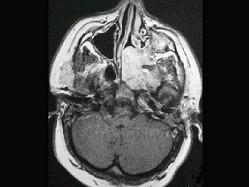

问题 男性,19岁,左侧鼻腔反复出血一年余,CT、MRI扫描如图所示,请选择最可能诊断 ( )

选项 A、鼻咽癌 B、鼻咽部淋巴瘤 C、鼻咽腔脓肿 D、鼻咽部青年纤维血管瘤 E、鼻息肉

答案 D